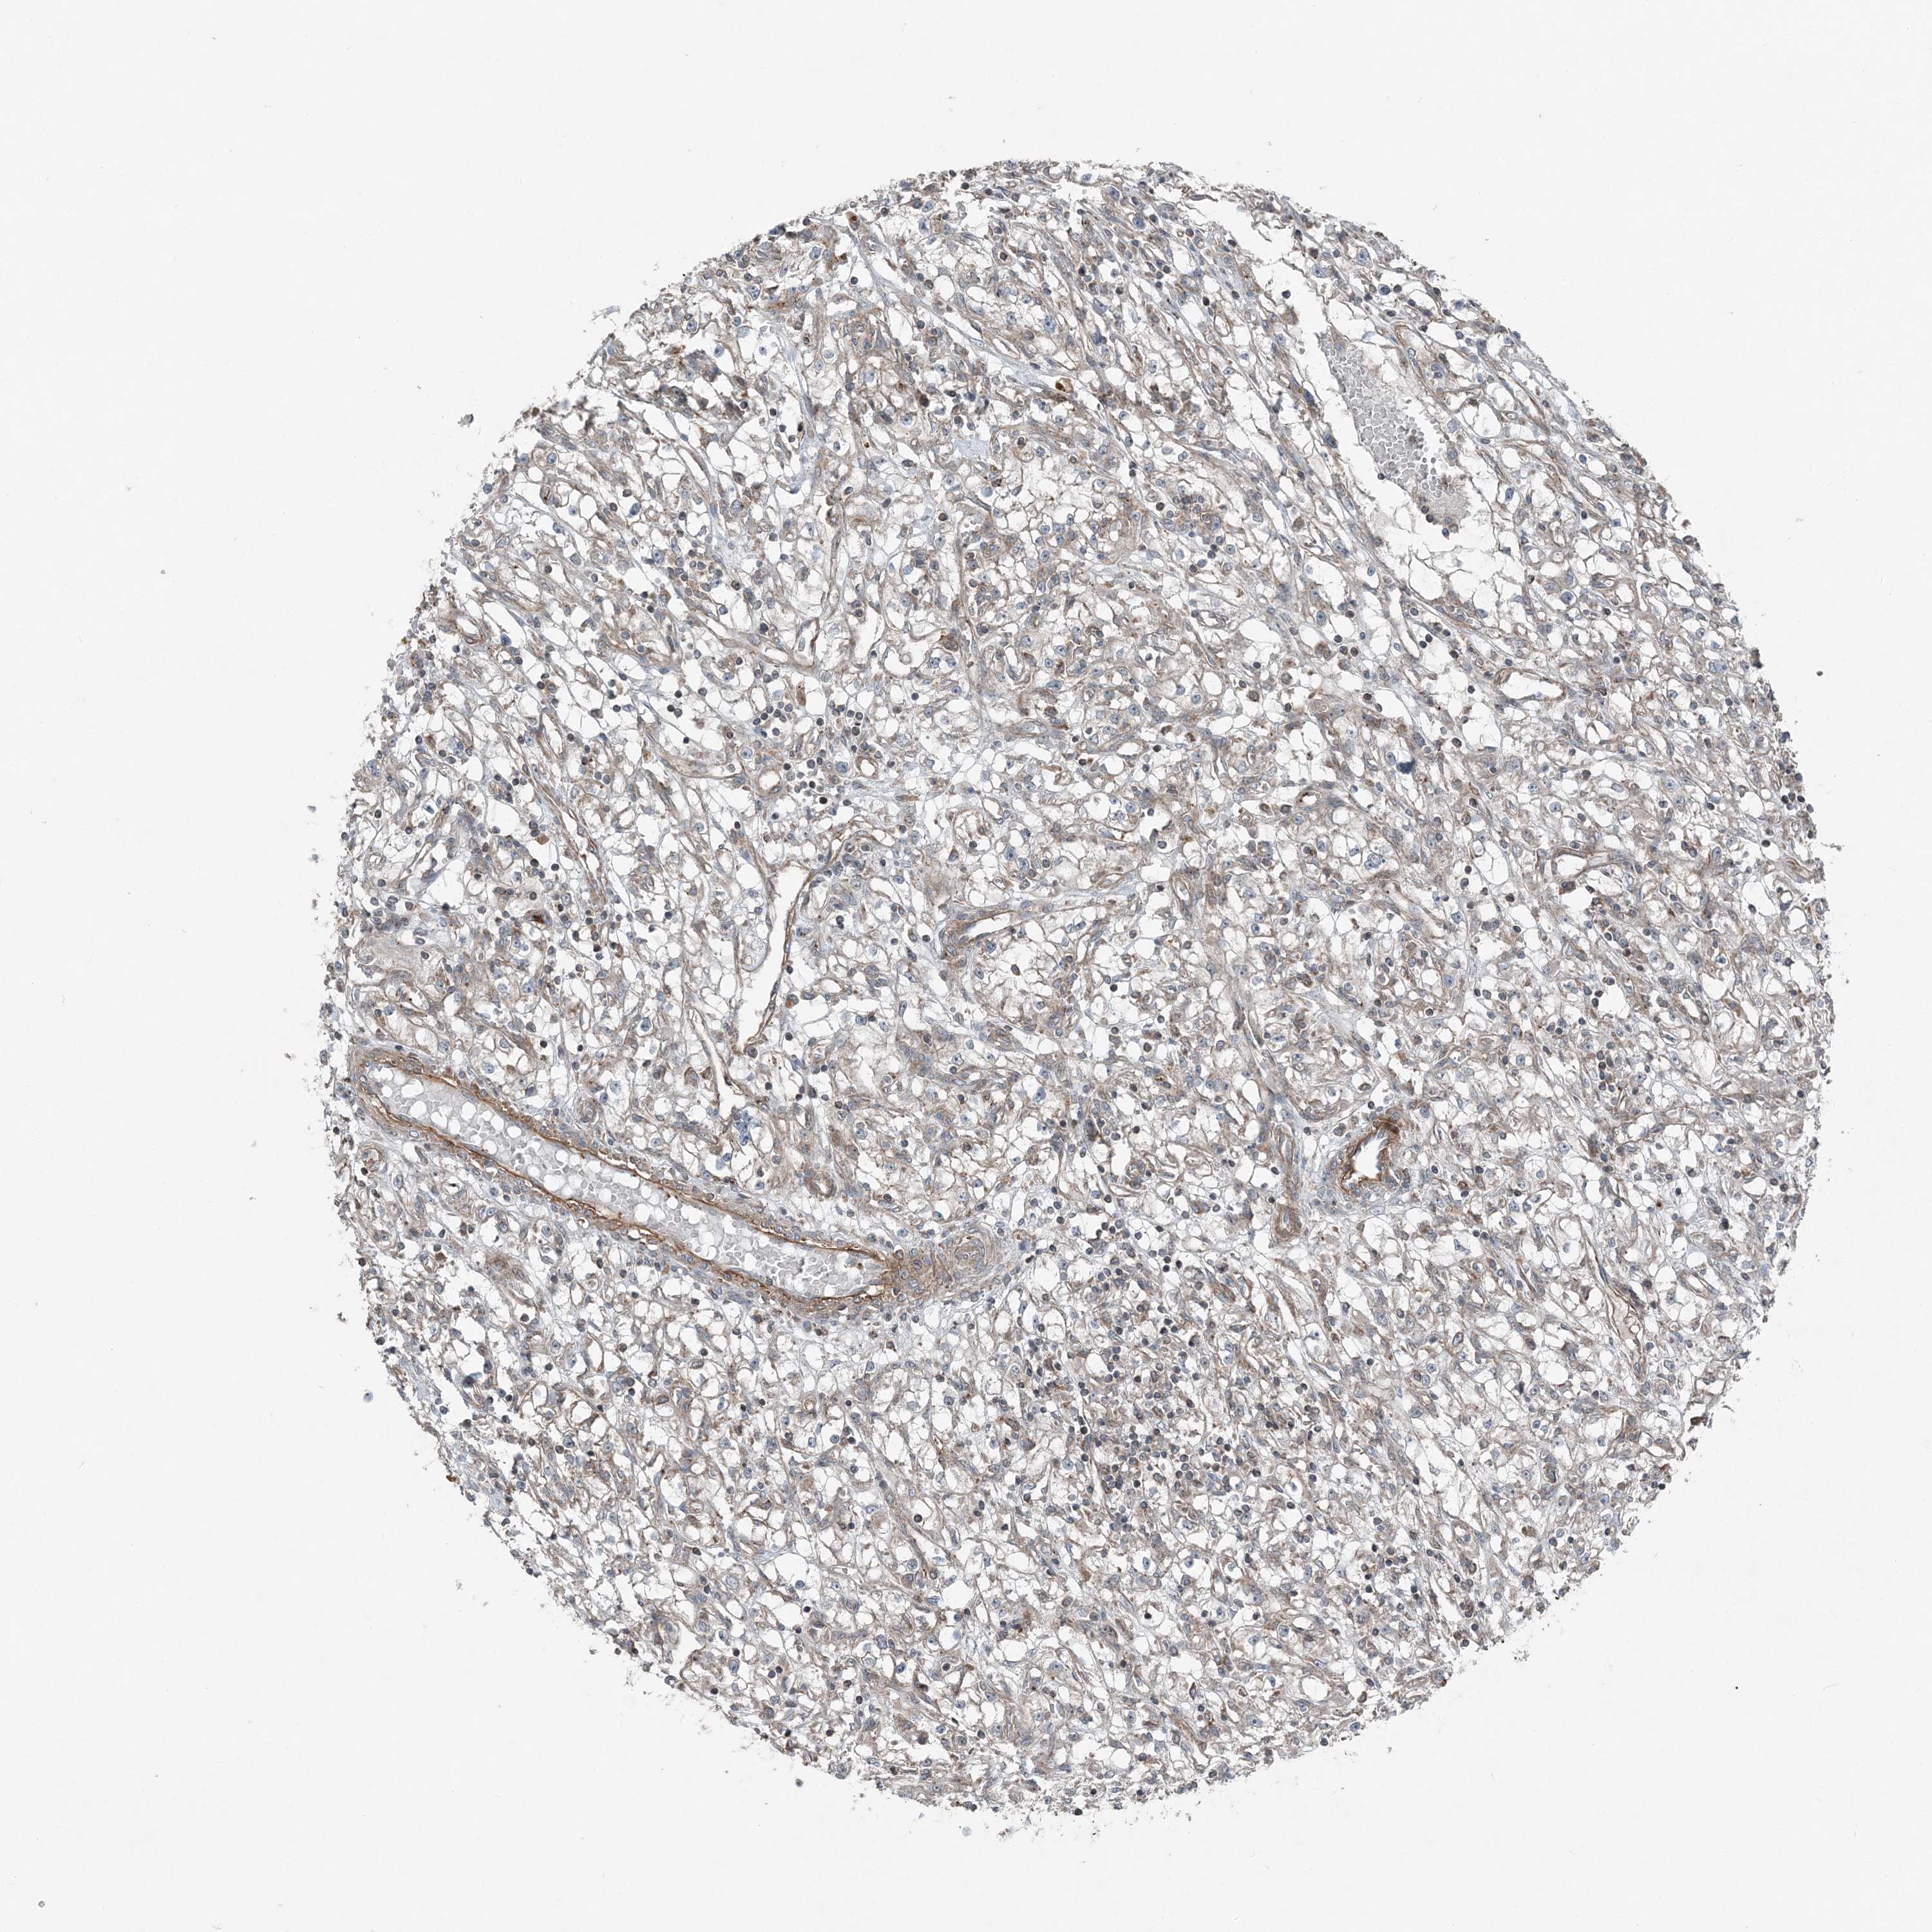

KIDNEY RENAL CLEAR CELL CARCINOMA (VALIDATION) - Interactive survival scatter ploti

The Survival Scatter plot shows the clinical status (i.e. dead or alive) for all individuals in the patient cohort, based on the same data that underlies the corresponding Kaplan-Meier plots. Patients that are alive at last time for follow-up are shown in blue and patients who have died during the study are shown in red.

The x-axis shows the expression levels (FPKM) of the investigated gene in the tumor tissue at the time of diagnosis. The y-axis shows the follow-up time after diagnosis (years). Both axes are complimented with kernel density curves demonstrating the data density over the axes. The top density plot shows the expression levels (FPKM) distribution among dead (red) and alive patients (blue). The right density plot shows the data density of the survived years of dead patients with high and low expression levels respectively, stratified using the cutoff indicated by the vertical dashed line through the Survival Scatter plot. This cutoff is automatically defined based on the FPKM cutoff that minimizes the p-score. The cutoff can be changed by dragging the vertical line or by entering a cutoff value in the square labeled "Current cut-off".

Under the Survival Scatter plot the p-score landscape (black curve; left axis) is shown together with dead median separation (red curve; right axis). Dead median separation is the difference in median mRNA expression between patients who have died with high and low expression, respectively. It is calculated as follows: median FPKM expression of dead patients with high expression - median FPKM expression of dead patients with low expression. This is intended to aid the user in visually exploring custom cutoffs and the associated p-scores and dead median separation.

Individual patient data is displayed and can be filtered by clicking on one or more of the category buttons on the top of the page. Categories describing expression level and patient information include: high, low, alive, dead, female, male and tumor stages. The scale of the x-axis can be toggled between linear and log-scale by clicking on the "x log" button. Mouse-over function shows TCGA ID, patient information and mRNA expression (FPKM) for each patient.

& Survival analysisi

Kaplan-Meier plots summarize results from analysis of correlation between mRNA expression level and patient survival. Patients were divided based on level of expression into one of the two groups "low" (under cut off) or "high" (over cut off). X-axis shows time for survival (years) and y-axis shows the probability of survival, where 1.0 corresponds to 100 percent.

KY is not prognostic in Kidney Renal Clear Cell Carcinoma (validation)

Average pTPM 0.3

Number of samples 100